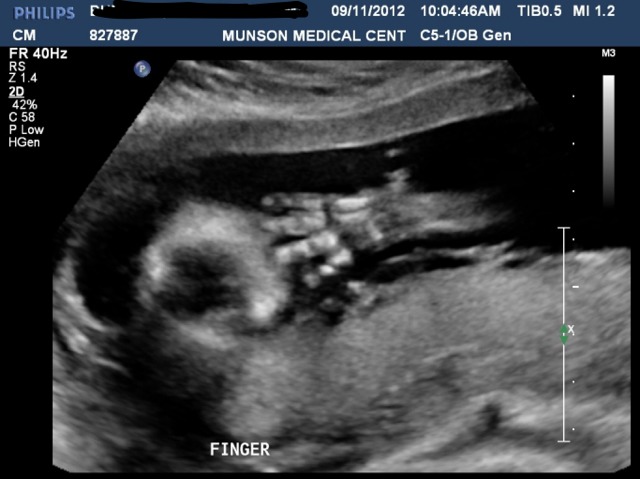

Hand in front of face, I thought this was the most amazing shot!

Attachment 4517